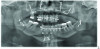

Fig 14. Postsurgical panographic radiograph showing surgical osteotomies and hardware stabilizing the maxilla, mandible, and chin in their new positions.

Figure 14

In contrast to soft-tissue surgery, greater success has been reported for surgery that increases upper airway size by repositioning anteriorally the maxilla and/or mandible (Figure 12 and 13). Maxillomandibular advancement surgery for OSA involves one or more of the following: Le Fort I osteotomy, in which the maxilla is moved forward; bilateral split sagittal osteotomy, in which the body of the mandible is moved forward; and anterior inferior mental osteotomy, in which the chin is moved forward (Figure 14).65,66,67 Orthodontics is required before and after the surgery. The surgery is usually reserved for patients with severe OSA who cannot tolerate CPAP, and has been reported successful in 65-100% of patients depending on the definition of success. Unlike CPAP and oral appliances, the surgery attempts to cure, rather than manage, OSA, and compliance to therapy is 100%.